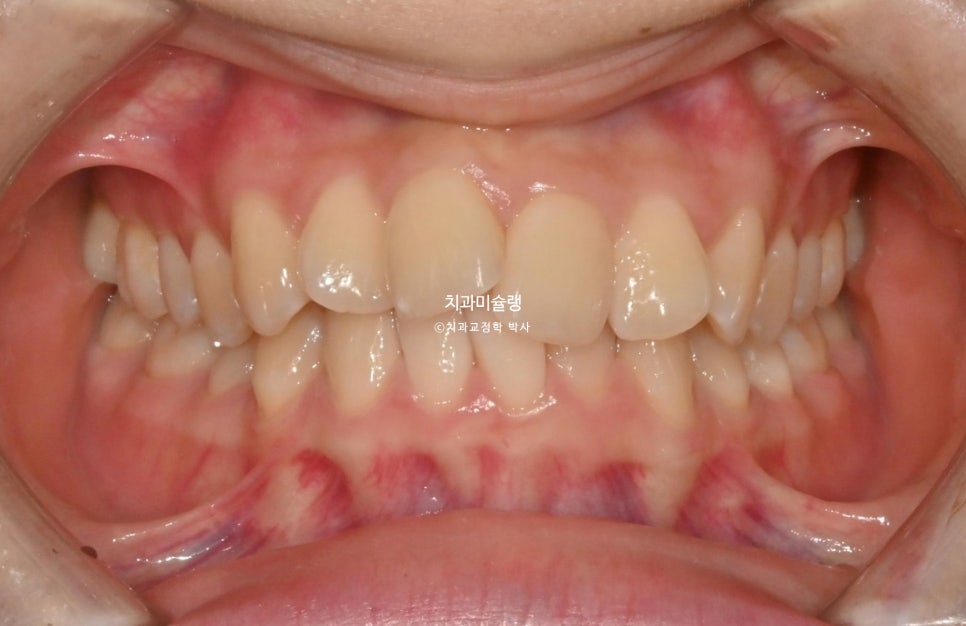

초진 상태 및 환자 요구사항

2025년 봄 초진

25년 봄, 교정치료를 위해 온 환자분 입니다.

위 아래 앞니가 삐뚤 삐뚤 합니다.

환자분이 고치고 싶은것은 앞니 배열이지만 스스로 통증에 예민한 편이니

작은어금니 발치나 사랑니 발치는 원치 않고 교정용 나사 (미니스크류)도 하고싶지 않으며 단지 배열만 목표로 교정을 하고 싶어 하셨죠.

아래 앞니가 1개 선천적으로 없는 3전치 입니다.

어금니는 가지런한 편입니다.